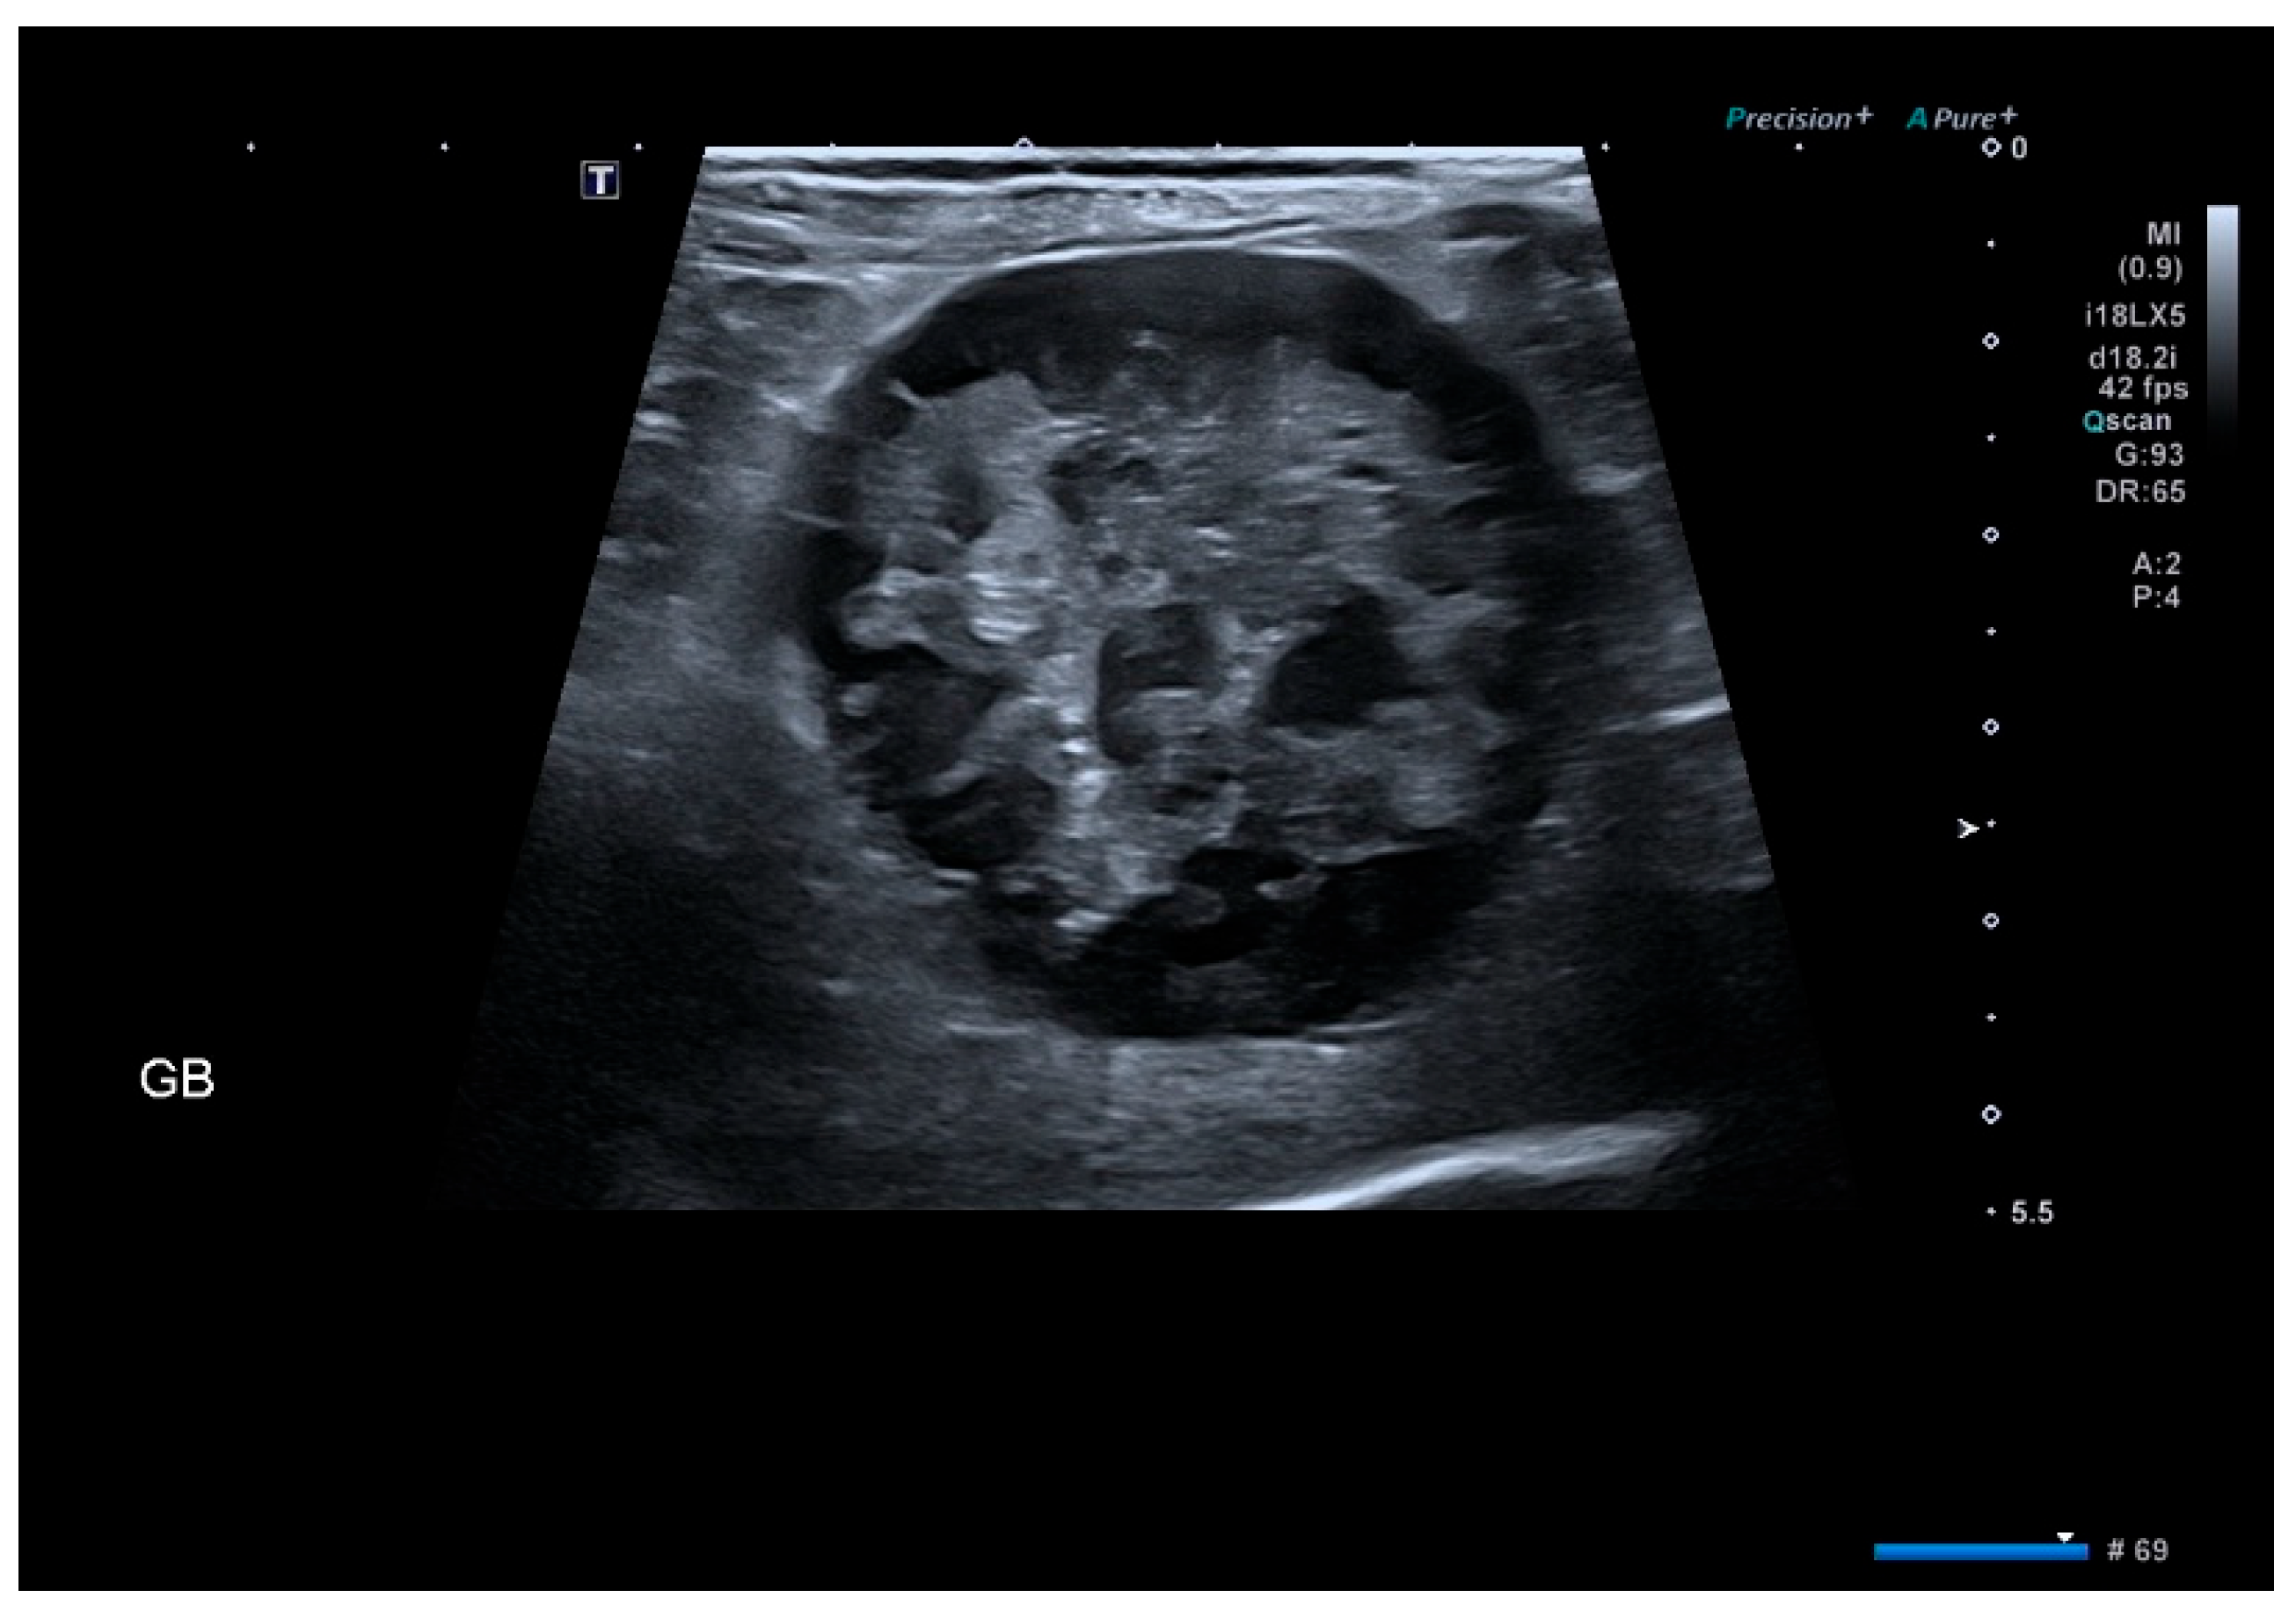

2.3. Imaging Evaluation

3.3. Ultrasound Findings